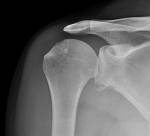

Shoulder dislocation

- anterior >95%

- subcoracoid (majority)

- subglenoid (1/3)

- subclavicular (rare)

- posterior 2-4%

- inferior (luxatio erecta) <1%

- post dislocations may be missed on AP film - transcapular view is therefore important if suspicious

- axillary N is the most commonly injured N - examine for signs of other brachial plexus injury also

- axillary art damage may also occur esp in the elderly